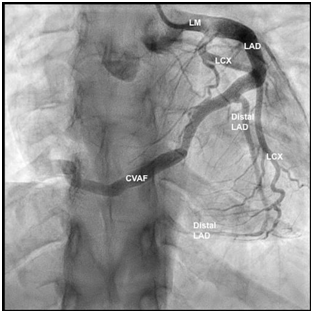

Transthoracic Echocardiography showed a good left ventricular ejection fraction of 60% with no significant regional wall motion abnormality. During the coronary angiography, she was found to have a dilatation in the left main stem extending to the mid-segment of the LAD. (Figure 3) (Figure 4).

Figure 3 Coronary angiography: Straight antero-posterior view: Dilatation of the left main (LM) stem extending to the proximal and mid- left anterior descending artery (LAD). The coronary arteriovenous fistula (CVAF) originating from distal LAD. Type III LAD wrapping around the left ventricular apex, supplying the apical two-thirds of infero-posterior wall.

There was an arterio-venous fistula, arising from the distal LAD with an unclear drainage end into the right heart chambers (Figure 3) (Figure 4). There was a slow flow in the distal LAD beyond the fistula origin. Her LAD was type III, wrapping around the left ventricular apex, supplying the apical two-thirds of infero-posterior wall. The right coronary artery (RCA) was rudimentary and the left circumflex artery (LCx) was normal. To further study these abnormalities, she was scheduled for CT Coronary Angiogram which revealed a fistula arising from the distal LAD and courses anteriorly on the right ventricle measuring 3.3 mm just after its origin from the LAD, terminating into the superior aspect of the right ventricle (RV). The terminal part of the AV measures 11.8 mm (Figure 5) (Figure 6). The rest of the coronary findings were matching those seen in the conventional coronary angiography.